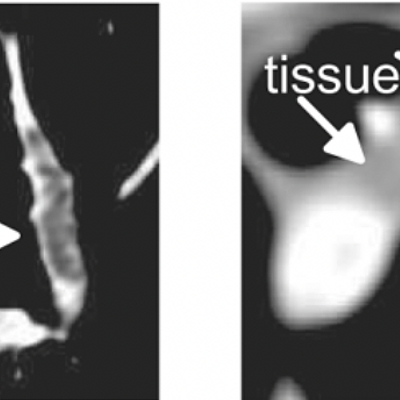

Two frames of a real-time animation sequence that conveys the uncertainty regarding the border between a cyst and a hemorrhage in an MR brain examination

Jan Klein, O. Friman, Markus Hadwiger, Bernhard Preim, F. Ritter, et al.

Computers & Graphics, 2009